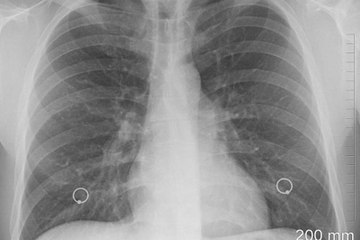

الالتهاب الرئوي عند الأطفال